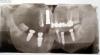

neuda4nik Опубликовано 4 июня, 2012 Автор Поделиться Опубликовано 4 июня, 2012 Добрый день. Удалось сбросить карточки на диск.Удивлён такому низкому разрешению исходников.Наверное установка древняя стоит с маленькой матрицей.Первая карточка сделана 27/01/2012, вторая 31/05/201236 и 37 помаленьку приживаются, уже практически не беспокоят. Сейчас видимо пару месяцев надо отдохнуть для восстановления кости на месте 16 и 17и снова пробовать крутить туда имплантаты? Ссылка на комментарий

neuda4nik Опубликовано 6 августа, 2012 Автор Поделиться Опубликовано 6 августа, 2012 Здравствуйте!Утром поставили 16 и 17На место 16 установили 11.5х3.5, а на 17 поставили 10.0х5.015 оставили жить на данном этапе.Доктор уплотнял кость - колотил молотком минут 10 наверное. Положили костный материал сверху, прикрыли мембраной, ушили, прописали Амоксиклав, Линекс и отправили домой Завтра с утра осмотр. Вот что имеем на данный момент - однако хороший зоопарк собрался http://db.tt/ld3t6IuQ 16 судя по картинке поставили в перегородку между 16 и 17 - там кости больше было.у него теперь будет номер 16.5 Доктор ручкой на картинке нарисовал предполагаемое расположение коронок. Если бы на месте 16 оказалось мало кости, имелся запасной вариант с удалением 15 и установкоймоста 15-17.5, но обделались малой кровью Имплантаты израильские - Hi-Tec НМВ всё прошло не плохо. Несколько удивило обезболивание.После укола доктор стал делать операцию буквально через 2мин.Никакой чувствительности не было - как обухом по голове.И отпустило очень быстро и резко часа через 1.5 - еле успел до кеторола добежать. Ссылка на комментарий

neuda4nik Опубликовано 8 августа, 2012 Автор Поделиться Опубликовано 8 августа, 2012 (изменено) Зравствуйте! Сегодня в обед, войска хирургического фронта взяли шурмом высоту №37 (прошло почти 2 месяца с момента её потери).Была произведена зачистка местности от вражеских грануляционных элементов, вкручен имплантат 5.0х10.0.Близлежайшая территория прикрыта исскуственным костным материалом и мембраной.Место оперички доктор обработал какой-то хитрой химией. Хвалился что пишет докторскую по этому препарату.Позавчерашнее место установки имеет бледно розовый цвет слизистой. Ни малейших следов воспаления.Хотя некоторый дискомфорт и небольшая припухлость наблюдается, видимо идёт заживление .Кеторол пил по одному разу после каждой операции, для облегчения процесса завершения обезбаливания.Ничего похожего на те боли, что были после предыдущих операций нет и близко. На сегодня имеем следующую картину. http://db.tt/53YVuxKJ На пятницу запланирован осмотр плацдарма у главнокомандующего с определением плана дальнейших мероприятий.Если всё приживётся (ТТТ) будем протезироваться.я таки их победю! Изменено 8 августа, 2012 пользователем neuda4nik Ссылка на комментарий